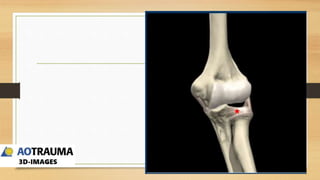

MEHNE Y JUPITER PARA

FRACTURAS ARTICULARES

EN H Y LAMBDA TIENE

MAYOR RIESGO DE NECROSIS

AVASCULAR

CLASIFICACION AO